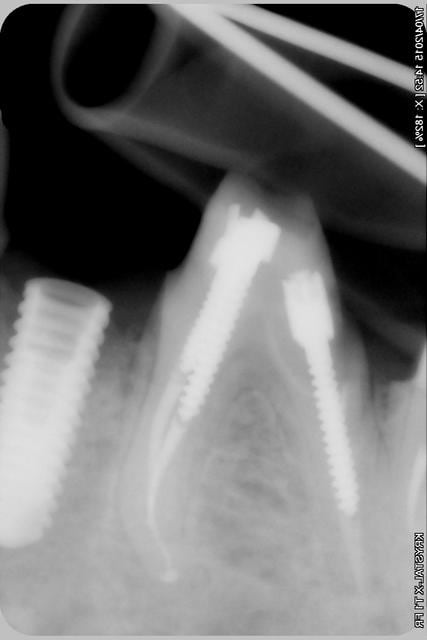

Nouveau patient, pose d'un implant il y a 2 mois....échec sans raisons particulières, douleurs et dépose.

Ce matin repose d'un nouvel implant et comme je ne veux pas prendre de risque, et que les dents adjacentes doivent être couronnées, je pose un bridge en emax press, mais scellé au ciment provisoire...

Si l'implant va bien le bridge sera déposé, coupé, et 44/46 seront collées définitivement après traitement acide et silane.

Si par hasard l'implant pose problème, dépose et bridge collé.

alors là pas du tout, le patient vient me voir pour des implants, donc je fais une étude du cas absence des molaires supérieures, couronnes mandibulaires très ancienne 45 racine cassée, 44 dévitalisée mais passablement déchaussée, donc avulsion de 45 et pose d'un implant avant de refaire les couronnes 46/47 et l'ensemble.

Échec implantaire, et oui ça arrive, même dans un cas paraissant simple.

Dépose gratuite bien sur et repose gratuite aussi, le bridge n'est pas facturé non plus, il le sera sous forme de 2 couronnes que cette fois ci l'implant fonctionne ce que j’espère, ou laissé en bridge si l'implant devait être retiré.

Le fait de scellé au ciment temporaire ne pose en principe pas de problème pour 3 à 6 mois.

Oui, un Px, le premier était un Reg.

l'os était tendre, ce qui explique le choix du Px